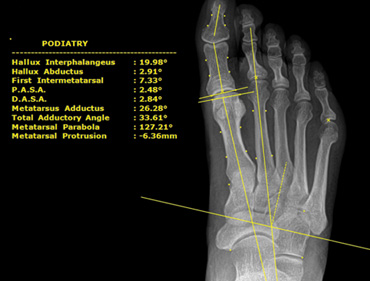

Viewer (see left)

- User friendly, DICOM compliant, DPM Tools ††

Podiatric Tool-Set††

- Hallux Interphalangeus

- Hallux Abductus

- First Intermetatarsal

- P.A.S.A.

- D.A.S.A.

- Metatarsus Adductus

- Total Adductory Angle

- Metatarsal Parabola

- Metatarsal Protrusion